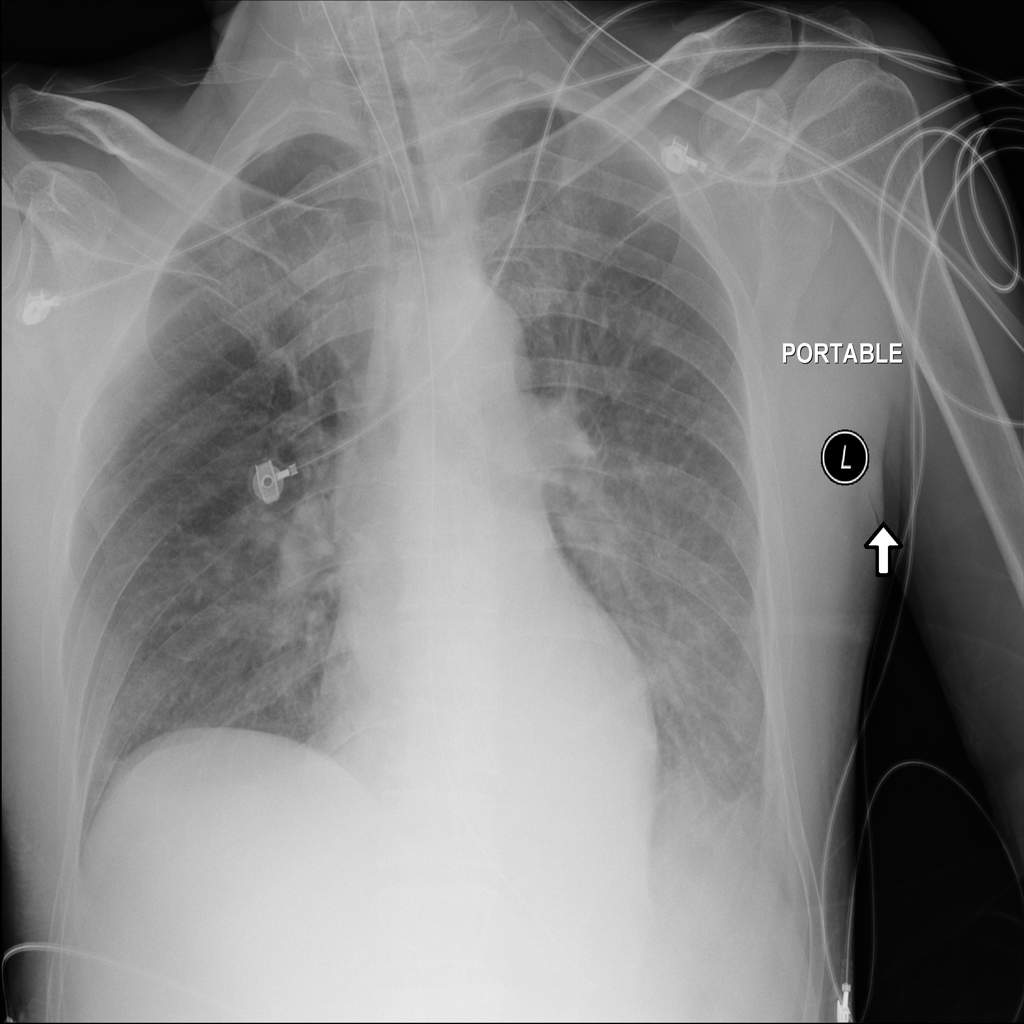

PAT-E828 · IMG-004Edema

PAT-E828 · IMG-004

AP